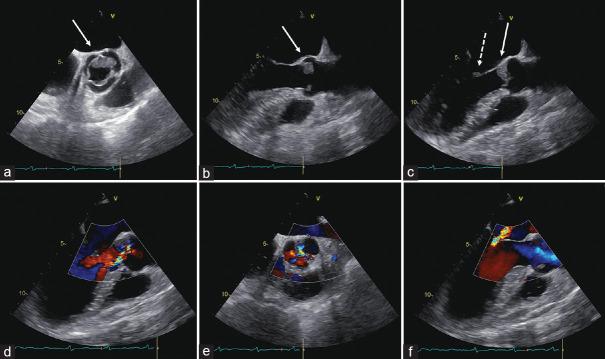

Nonbacterial thrombotic endocarditis (NBTE) is a rare condition that refers to a spectrum of noninfectious lesions of cardiac valves that is most commonly seen in advanced malignancy. We describe a case report of a 63-year-old male with NBTE and multiple embolizations (encephalic, coronary, splenic, and renal). The patient was admitted to the emergency department for stroke. During hospitalization, the patient complained of left leg pain and a venous echo color Doppler of the lower limbs was performed, showing bilateral distal deep-vein thrombosis. A thoracoabdominal computed tomography scan, which was performed to rule out pulmonary embolism, revealed a primary lung cancer and subcarinal lymphadenopathy. As collateral findings, multiple ischemic lesions in the spleen and in both kidneys were identified. In addition, areas of subendocardial hypodensity compatible with ischemia were also highlighted. An electrocardiogram showed acute myocardial infarction and focused echocardiographic evaluation displayed hypokinesis of the lateral and posterior in the mid- and distal segments and aortic and mitral valve vegetations, confirmed by a transesophageal echocardiography. Empiric antimicrobial therapy was started; all blood culture sets were negative and the patient was apyretic throughout the hospitalization. These findings supported the hypothesis of NBTE with multiple embolizations during a hypercoagulable state associated with advanced lung cancer.

非细菌性血栓性心内膜炎(NBTE)是一种罕见疾病,指一系列心脏瓣膜的非感染性病变,最常见于晚期恶性肿瘤患者。我们报告一例63岁男性患有NBTE并发生多处栓塞(脑部、冠状动脉、脾脏和肾脏)的病例。该患者因中风入住急诊科。住院期间,患者诉左腿疼痛,遂行双下肢静脉彩色多普勒超声检查,结果显示双侧远端深静脉血栓形成。为排除肺栓塞而进行的胸腹计算机断层扫描显示原发性肺癌及隆突下淋巴结肿大。作为附带发现,脾脏和双肾发现多处缺血性病变。此外,还发现了与缺血相符的心内膜下低密度区域。心电图显示急性心肌梗死,经食管超声心动图证实,聚焦超声心动图评估显示中段和远端节段的侧壁和后壁运动减弱以及主动脉瓣和二尖瓣赘生物。开始经验性抗菌治疗;所有血培养结果均为阴性,患者住院期间未发热。这些发现支持了在与晚期肺癌相关的高凝状态下发生NBTE并伴有多处栓塞的假说。